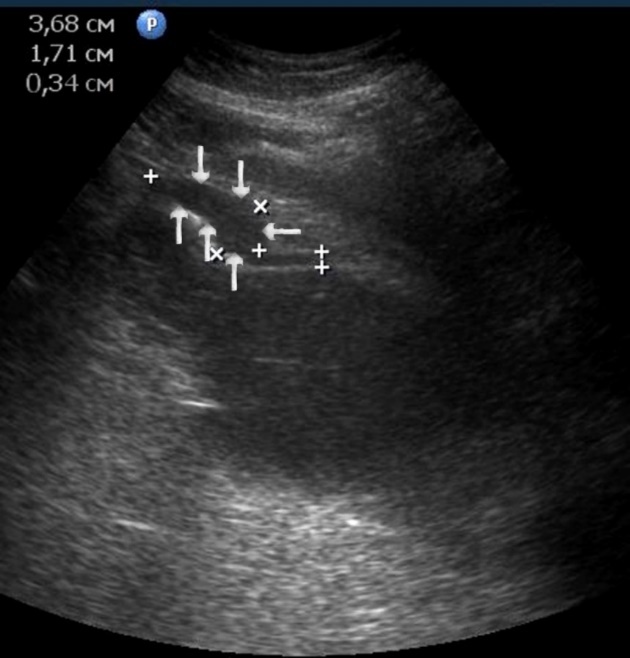

Figure 10.The gastric carcinoma of diffuse infiltrative form. An area with a local thickening up to 1,7 cm, a length of 3,68 cm, is visualized on the anterior wall of the antrum (arrows). The thickening of the normal stomach wall is 0,34 cm.

T3 stage of polypoid form was recorded in one case, ulcerative form – in 11 cases, infiltrative ulcerative forms – in 21 cases and diffused infiltrative forms – in 8 cases. The Sonographic features of infiltrative ulcerative form of gastric carcinoma was shown as local uneven thickening of the stomach wall with a length of up to several centimeters with intermittent images and ulceration of the mucosa (Figure 11). The Ulcerative form of gastric carcinoma was shown as a raised margins surrounded by a thickened gastric wall with irregular margins (Figure 12). Gastric carcinomas of diffuse infiltrative form is illustrated as a diffuse thickening of the muscle layer, a smooth contour, discontinuous mucosal image without ulceration and involvement of the serous membrane in the process (Figure 13).